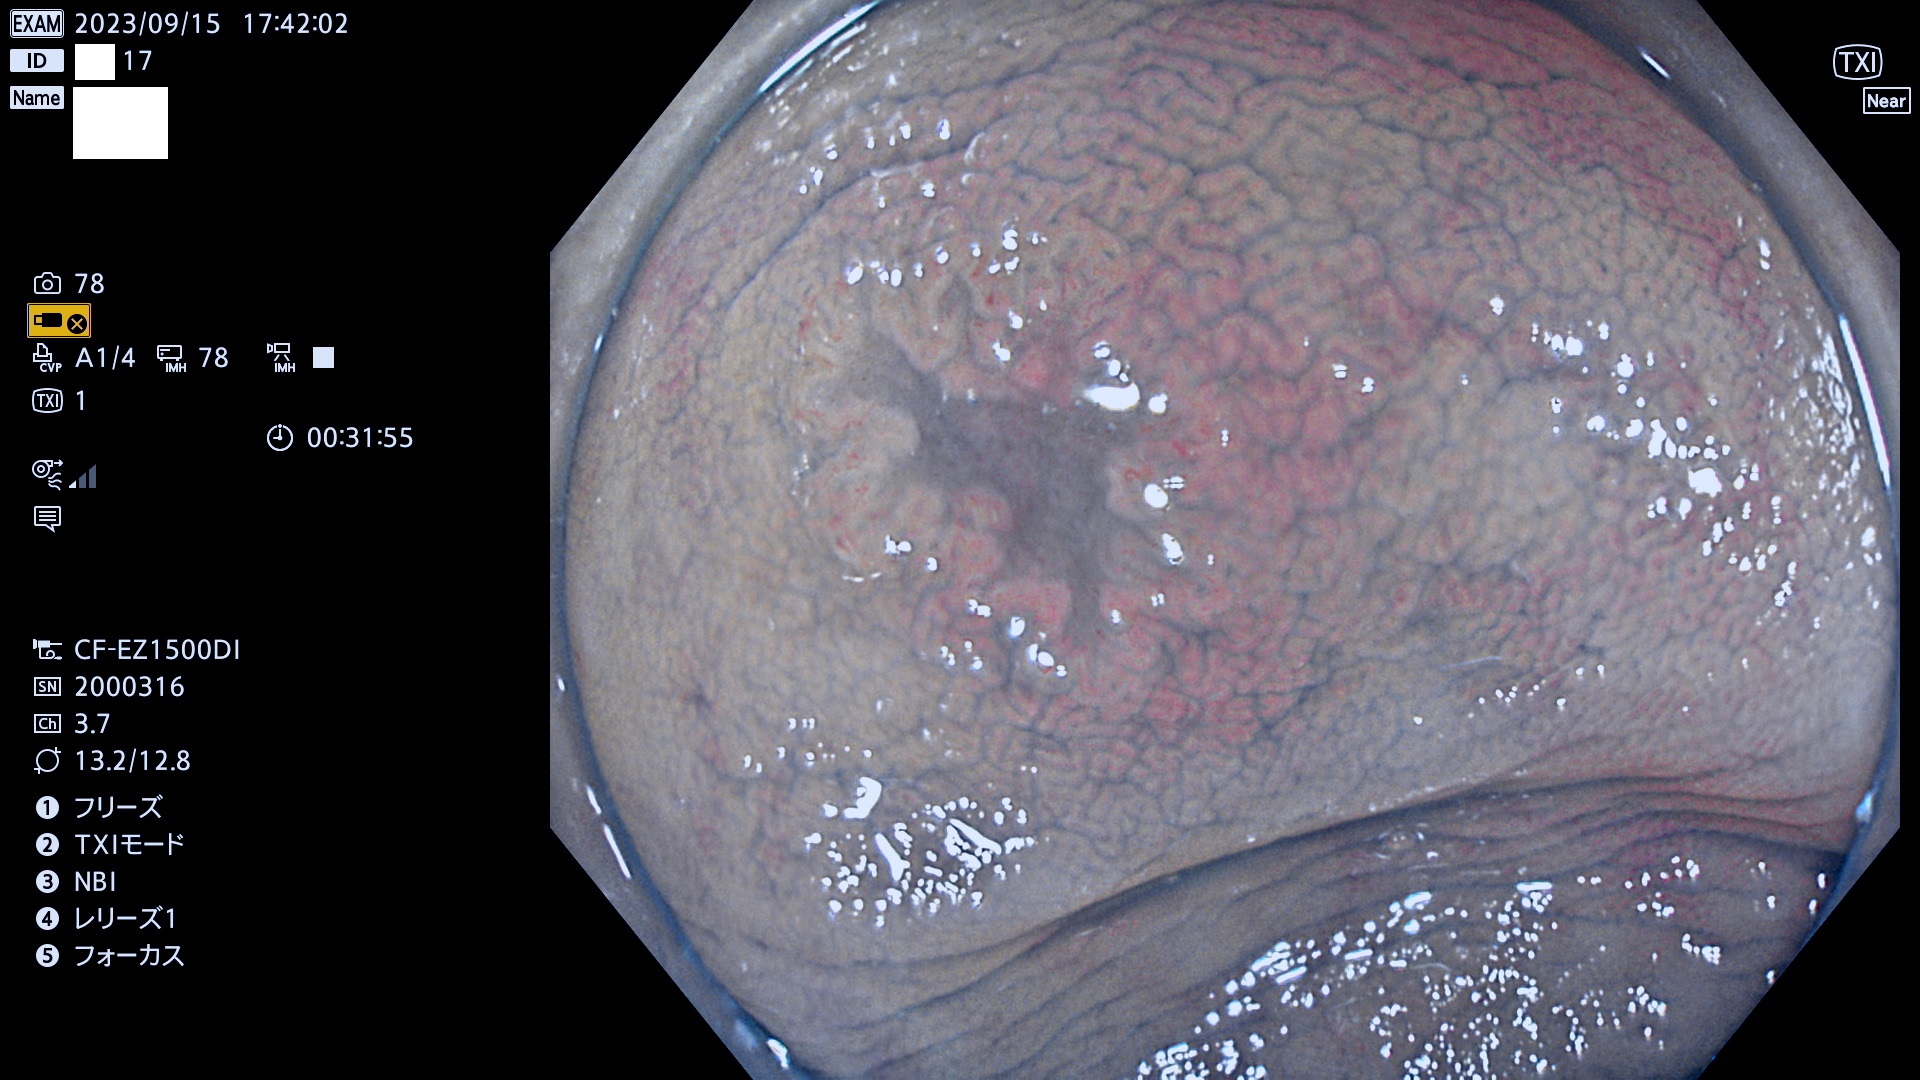

表面型腺腫(Flat Adenoma)の中で、完全に平坦な物をUb、陥凹している物をUcと呼びます。平坦隆起型(Ua)よりも、発見が難しく危険な病変です。このタイプは「内視鏡後・大腸癌の重要犯人」であり、この発見率は「腺腫発見率」よりも、重要な意味があります。

毎週の検査(木・金・土・日)に発見されたUb、Uc型・腺腫を、その週の日曜の夜にUPし1週間、提示します。

抽出の対象期間 2023年9月14日(木)〜9月17(日)の4日間(48件の検査)7件